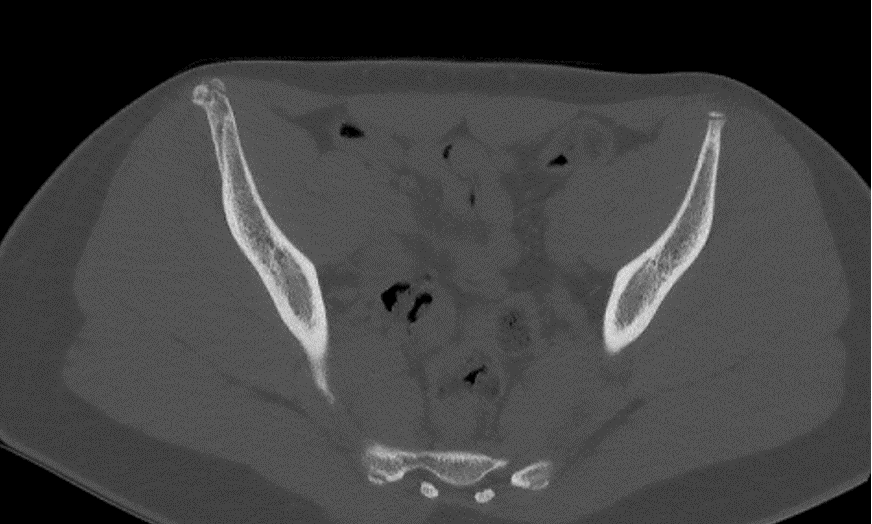

During follow-up, a spontaneous snapping was noted at the AIIS during activity, associated with mild bony hypertrophy at the avulsion site, confirmed on CT and MRI. No persistent pain or joint impingement was observed. The bony hypertrophy represented an adaptive consolidation response and did not impair functional recovery (Figures 1-6).

Figure 5. Pelvic CT scan at 6 months post-traumatic.

Figure 6. Pelvic CT scan at 6 months post-traumatic.